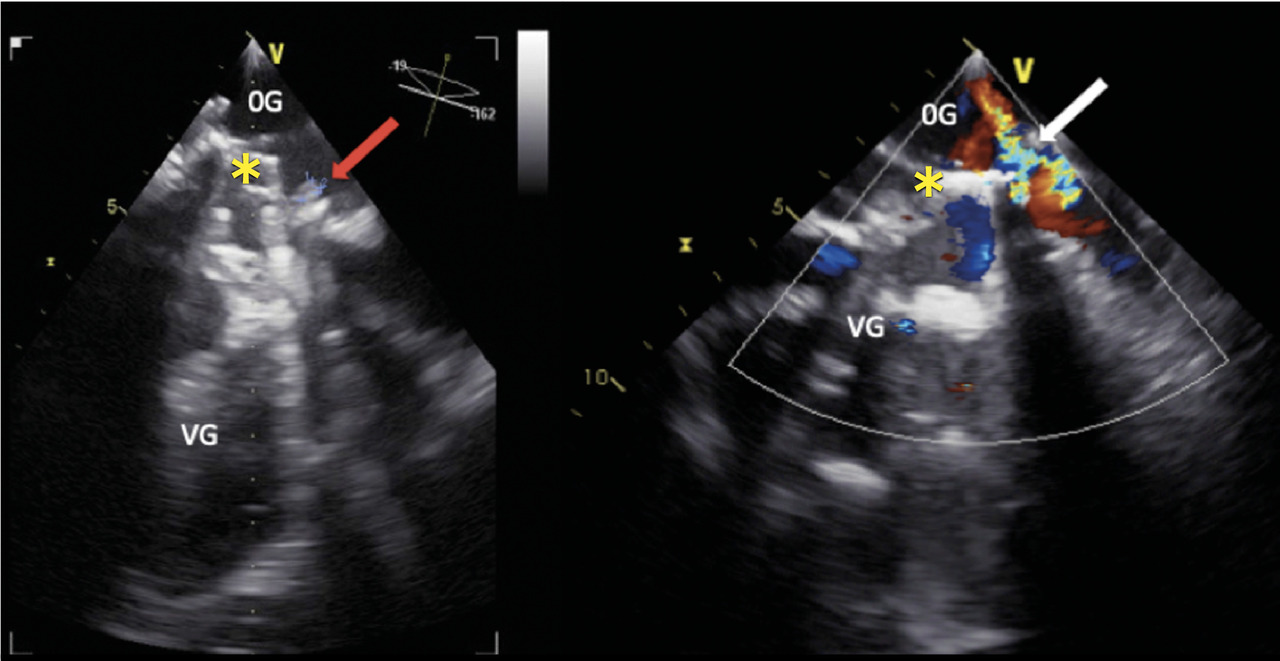

Cette femme de 67 ans avait une asthénie et par intermittence des urines sombres. Une insuffisance mitrale rhumatismale avait été traitée 22 ans auparavant par remplacement valvulaire chirurgical. Le bilan biologique révélait une anémie (7,6 g/dL) normochrome normocytaire régénérative (taux de réticulocytes à 278 000/mm3), un taux de lacticodéshydrogénase à 2 688 UI/L, un taux d’haptoglobine inférieur au seuil de détection et un taux normal de bilirubine totale. Le frottis sanguin (fig. 1 ) notait de très nombreux schizocytes (plus de 500/1 000). L’échocardiographie transœsophagienne (ETO)montrait la présence d’une végétation et une fuite prothétique (fig. 2 ). Il s’agissait d’une endocardite infectieuse à Pseudomonas aeruginosa compliquée d’une désinsertion de valve prothétique.

Les schizocytes, fragments circulants d’hématies, sont caractéristiques de l’hémolyse mécanique, telle que la microangiopathie thrombotique.1 Une hémolyse infraclinique chronique peut être présente en cas de valve prothétique de fonctionnement normal. Son incidence tend à diminuer du fait des améliorations de conception des prothèses.2 Un syndrome anémique ou des stigmates biologiques témoignent d’un dysfonctionnement ou plus fréquemment d’une fuite paraprothétique.3 L’hémolyse résulte de forces de cisaillement en lien avec la turbulence du flux.2 Une fuite paravalvulaire tardive traduit souvent une déhiscence de suture, favorisée par la calcification annulaire ou causée par une infection.3